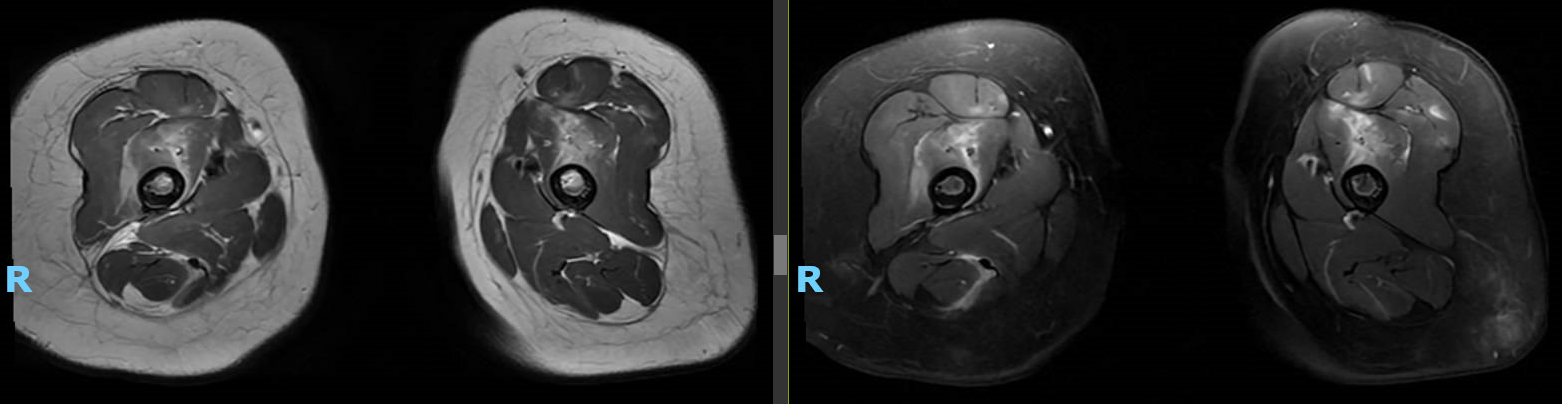

Case Presentation: A previously healthy 16-month-old girl presented to the emergency department with refusal to walk following a fall. She was lowering herself from a high bed when she fell backwards, hitting her buttocks and lower back without a head strike. Over the next couple days, the patient was fussy and less active. She refused to stand or walk and was eating less than normal. Prior to the fall, she had been meeting developmental milestones appropriately and walking without issue. The patient had rhinorrhea the week prior but no recent fever, cough, dyspnea, vomiting, diarrhea, abdominal pain, or rash. On exam she was afebrile with vitals within normal limits. She appeared uncomfortable with tender swelling of the midline lower thoracic region. She had full range of motion and appropriate strength of all extremities but cried with movement of the legs. Tone and reflexes were normal. When placed upright, her legs would stiffen and she would plantarflex before falling to a crouching position. Initial labs were notable for elevated ESR (57) and AST (102) with otherwise normal CBC, CMP, and CK. Radiographs of the thoracic spine, sacrum, and lower extremity were unremarkable as was total spine MRI. The patient was admitted for observation but showed minimal improvement despite administration of acetaminophen and ibuprofen. Given she was still far from baseline after a week, MRI of the brain and lower extremity were obtained which showed extensive inflammation of the pelvic girdle, thighs, and legs (see image).

Discussion: The differential diagnosis for this toddler with prolonged refusal to walk following a fall was initially broad, including trauma, infectious/inflammatory etiologies, neurologic disorders, toxic exposure, and hematological disease/malignancy. The failure of symptoms to improve prompted imaging revealing extensive muscle inflammation suggestive of an inflammatory (post-viral or autoimmune) vs. non-inflammatory myopathy. Further labs at this time were notable for continued normal CK and elevated AST with aldolase and LDH elevated (hemolyzed). An extended myositis panel revealed positive anti-MDA5 antibodies, and muscle biopsy confirmed diagnosis of juvenile dermatomyositis (JDM). JDM is a rare, autoimmune disease characterized by proximal muscle weakness and classic skin rashes but can affect multiple organ systems. Serologic testing may demonstrate elevated muscle enzymes and presence of myositis-specific/myositis-associated antibodies (1). Prevalence of anti-MDA5 antibodies in JDM patients varies based on ethnicity (7% in predominantly Caucasian cohorts vs. 38% in a Japanese cohort) and the associated clinical phenotype has been shown to include cutaneous lesions and interstitial lung disease with milder muscle disease and lower CK levels (2,3). Several aspects of this patient’s presentation were notable including the lack of characteristic skin lesions (e.g. Gottron’s papules, heliotrope rash, skin ulcerations) at the time of presentation as well as the young age at onset of symptoms (average onset of JDM is 7 years and anti-MDA5 antibodies have been associated with later onset of symptoms) (1,2).